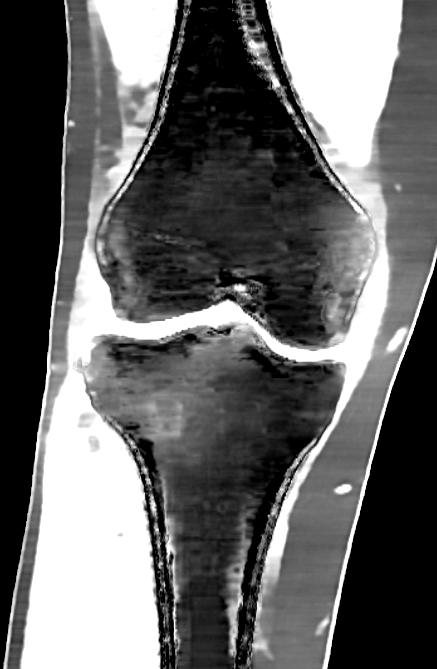

Bild 3. En 45-årig patient med smärtsymtom i mediala kompartment. T2-mappning av brosk i knäet visade förtjockning och förändrad brosksignal (pilar) som är förenligt med skada/degeneration. Dock är degeneration av brosk i främre delen (böjd pil) också synlig, vilket ännu inte syns på konventionella sekvenser. Denna undersökning möjliggör bedömning av tidiga artrosförändringar innan de blir synliga på konventionella sekvenser.